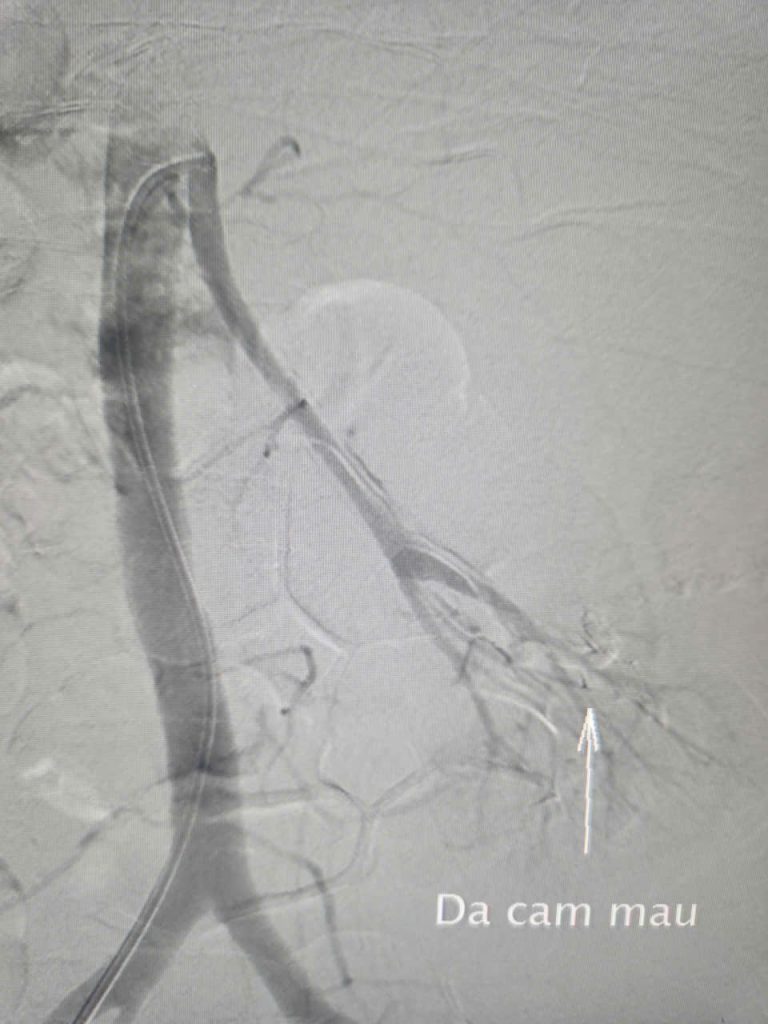

Hình ảnh vị trí chảy máu

Hình ảnh mạch máu sau can thiệp tắc mạch

Dưới sự hướng dẫn của hệ thống DSA, ê – kíp luồn một ống thông nhỏ qua động mạch đùi, đi đến nhánh động mạch thận trái nuôi khối bướu, sau đó tiến hành nút tắc mạch máu bị vỡ bằng vật liệu chuyên dụng.

Trong vòng 45 phút, các bác sĩ đã khống chế tình trạng chảy máu và ngăn chặn hiệu quả nguồn máu nuôi bướu nhằm làm teo nhỏ khối bướu về sau.